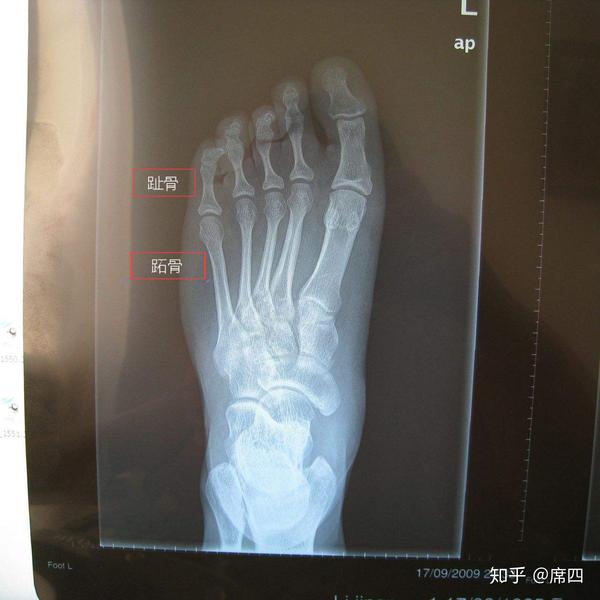

高弓足扁平足足内翻足外翻有啥关系? 知乎